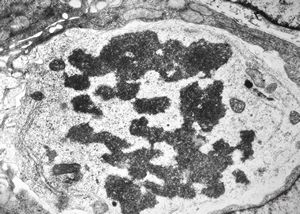

F,35y. | mitosis - intestine, celiakia